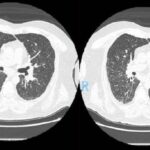

La sarcoidosis pulmonar se caracteriza por varios hallazgos en la tomografía computarizada de alta resolución (TCAR). Estos incluyen linfadenopatía hiliar y paratraqueal bilateral bien definida, opacidades nodulares y micronodulares con distribución perilinfática. Los nódulos son redondeados y suelen tener un tamaño de 2 a 4 mm. También se observa el agrandamiento y calcificación de los ganglios linfáticos hiliares bilaterales. Las calcificaciones pueden presentar diferentes aspectos, como amorfo, puntiforme (parecido a una palomita de maíz) o similar a una cáscara de huevo. La distribución perilinfática de las lesiones micronodulares es el patrón parenquimatoso más frecuente. Con el tiempo, estas lesiones pueden fusionarse y formar macronódulos y conglomerados similares a masas, con la presencia de pequeños nódulos satélites alrededor de las masas conglomeradas, lo que se conoce como “signo de galaxia”.

En la TCAR se pueden encontrar otros hallazgos menos frecuentes, como cambios fibróticos con opacidades lineales y bronquiectasias por tracción, opacidades parcheadas en vidrio esmerilado, consolidación parcheada del espacio aéreo (alveolitis sarcoide o sarcoidosis alveolar), opacidades reticulares lineales aisladas, halo inverso o signo del atolón. La sarcoidosis pulmonar también muestra un patrón de atenuación en mosaico debido a la afectación granulomatosa o fibrosis de las vías respiratorias pequeñas, lo cual puede estar asociado con obstrucción en las pruebas de función pulmonar. El atrapamiento de aire es común pero no específico de la sarcoidosis y puede estar presente en cualquier etapa radiográfica de la enfermedad. Se detectan anomalías traqueobronquiales en la TC, con engrosamiento y estenosis de la pared bronquial, que se correlacionan con los hallazgos broncoscópicos.

La estenosis bronquial puede ser causada por acumulación de granulomas endobronquiales, compresión extrínseca de las vías respiratorias debido a ganglios linfáticos agrandados en el mediastino, o distorsión de los bronquios debido a enfermedad parenquimatosa fibrótica en etapa terminal. El bronquio del lóbulo medio derecho es el más afectado en la sarcoidosis. En casos avanzados y de alto riesgo, la TCAR puede mostrar quistes fibróticos, ampollas y enfisema paracicatricial, que indican una etapa avanzada de la sarcoidosis. Estas lesiones tienden a afectar las zonas pulmonares superiores y medias, siguiendo las vías respiratorias más grandes en una distribución perihiliar. Los cambios quísticos subpleurales en panal se encuentran principalmente en las zonas pulmonares superiores y medias, mientras que las bases pulmonares se ven menos afectadas. Se debe considerar la fibrosis pulmonar idiopática en el diagnóstico diferencial cuando las bases pulmonares están involucradas.

En la tomografía computada de tórax en ventana pulmonar se identifica un patrón micronodular con distribución perilinfática y difusa en ambos hemitórax. Este hallazgo se acompaña de un engrosamiento peribronquial notable, así como de opacidades en vidrio deslustrado, que predominan en las zonas subpleurales y en las regiones posteriores de ambos pulmones.

En la tomografía computada de tórax en ventana mediastínica se observan múltiples adenopatías localizadas en diversas áreas del cuello y mediastino. Estas adenopatías se distribuyen en las cadenas yúgulo-carotídeas, en ambas regiones supraclaviculares y a lo largo del mediastino, abarcando específicamente las siguientes áreas: la región paratraqueal superior derecha, los espacios retrocavo-pretraqueal y prevascular, la zona subcarinal, la ventana aortopulmonar y en la región de la arteria mamaria (AM). La presencia de estas adenopatías sugiere un compromiso linfático difuso en estas zonas.